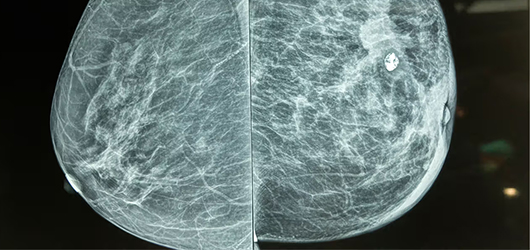

We deliver accurate mammogram results with high-definition clarity, using advanced imaging systems that enable fast breast diagnostics and timely reporting for both routine screenings and detailed evaluations. We prioritize patient comfort, safety, and privacy at every step. From early detection of abnormalities to follow-up assessments, our experienced radiologists and technicians provide precise, timely reports to support confident clinical decisions. Trusted by physicians for reliable breast health insights, our mammograms aid in accurate diagnosis and effective treatment planning.